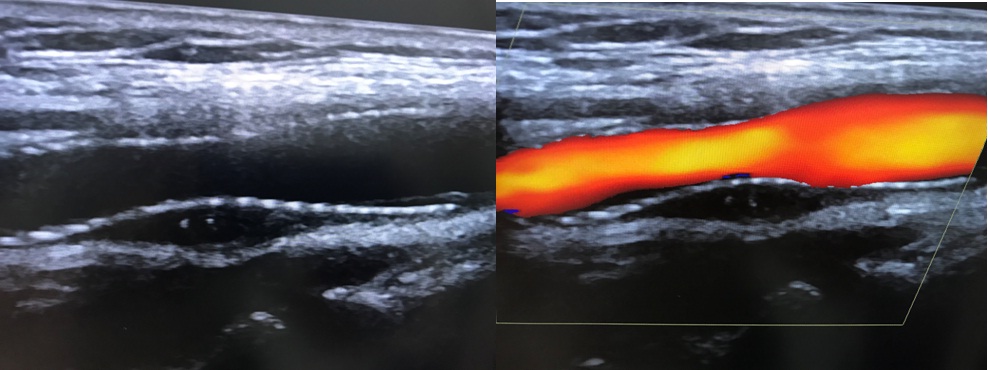

+ Siêu âm Động mạch cảnh: Hẹp động mạch cảnh trong phải đoạn gốc # 70%.